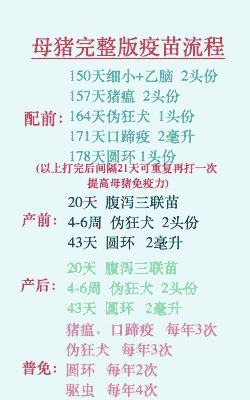

母猪产后打针消炎的效果因使用的药物种类和给药方式的不同而有所差异。以下是一些常见的用药建议及其效果:

常规用药

青霉素、 林可霉素、 头孢等抗生素一般一天一针,连续打三天效果最佳。

产后太保针,含有进口头孢和中药鱼腥草,一般连续使用三天可以起到较好的消炎效果。

中药注射

鱼腥草注射液、 银黄注射液、 板蓝根注射液等中药可以肌注一次,后续可以改为拌料给药,预防母猪产后炎症。

综合用药

头孢噻呋钠粉针、 恩诺沙星、 缩宫素等药物混合肌注,连续三天,同时配合饲料中添加益母生化颗粒、林克大观霉素等,连用7天,可以有效预防母猪产后炎症。

其他建议

产后当天肌注一次抗菌素针剂,后续可以改为拌料给药,以达到更好的消炎效果。

如果母猪阴部有粘液或脓液流出,需要持续用药直到症状消失。

建议

早期用药:建议在母猪产前一到两天开始使用消炎药物,特别是在产仔后的8小时内进行肌注,以预防感染。

综合措施:除了打针外,还可以通过拌料、饮水中添加药物等方式进行综合消炎,以达到更好的效果。

观察症状:在用药期间,应密切观察母猪的临床症状,如有异常应及时调整用药方案。

请根据具体情况选择合适的药物和给药方式,并在专业兽医的指导下进行操作。